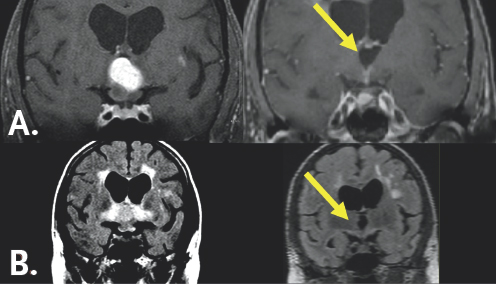

FIGURE 9.1 Pre-operative MRI. MRI (A) demonstrates a chordoid glioma (yellow arrow) occupying the confines of the third ventricle that appears bright after being injected with contrast. The underlying optic nerves and chiasm are swollen and infamed. MRI (B) shows extensive tissue damage associated with the mass (yellow arrow) that appears as a bright signal.

FIGURE 9.2 Post-operative MRI. MRI (A) imaging pre- (left) and post- (right) operatively. The yellow arrow points to the third ventricle after the brightly appearing tumor was removed. The optic apparatus, seen below the third ventricle, has returned to normal size following tumor removal. MRI (B) shows significant improvement in the tissue damage associated with the tumor seen by the bright white signal pre- (left) and post- (right) operatively. The yellow arrow highlights the lack of inflammation in this region after the tumor excision.